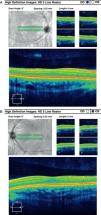

ResultsSD-OCT results revealed the presence of multiple inner retinal layers within the foveal region and symmetric thickening consistent with foveal hypoplasia of both eyes (Fig. 1A and B). The subject demonstrated MPOD levels of 0.10 at the fovea, 0.03 at 2°, 0.01 at 4° and undetectable at 6° of eccentricity in the RE. MPOD results for the study sample included mean values of 0.34 at the fovea, 0.15 at 2°, 0.09 at 4° and 0.03 at 6° of eccentricity in the RE. OriginPro9 software was used to fit the MPOD spatial distribution pattern to a Lorentzian function for both the subject and the study sample. Differences in the area under the curve and spatial distribution can be seen in the MPOD profile of the subject versus study sample (Fig. 2A and B). The subject demonstrated a mean intraocular scatter value of 1.28 while intraocular scatter values from study sample showed a mean value of 0.78 with a σ=0.13.

OCA affects the eyes, skin, and hair and may be tyrosinase-negative or tyrosinase-positive, and follows autosomal recessive inheritance patterns. Cardinal signs of OCA from a SD-OCT evaluation include absence of a central foveal depression, presence of the nerve fiber layer, ganglion cell layer, and other inner retinal layers across the fovea, and increased reflectivity of the choroid due to reduced levels of melanin.7